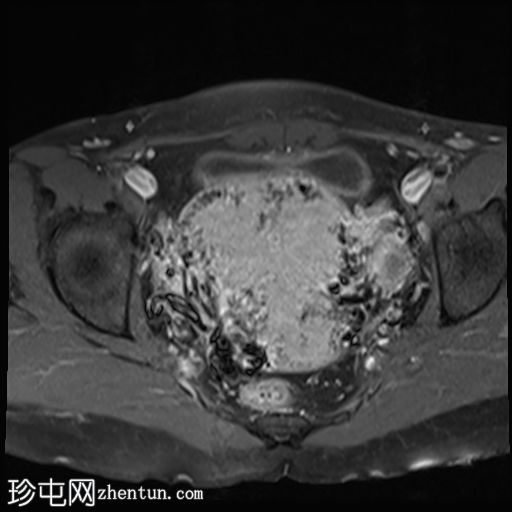

轴位T1加权像

增强脂肪抑制像

子宫增大且体积较大。扩张的血管主要位于子宫后壁(符合子宫动静脉畸形)。

子宫内膜肌层交界处也存在异常。

子宫内膜腔显影清晰,外观正常。